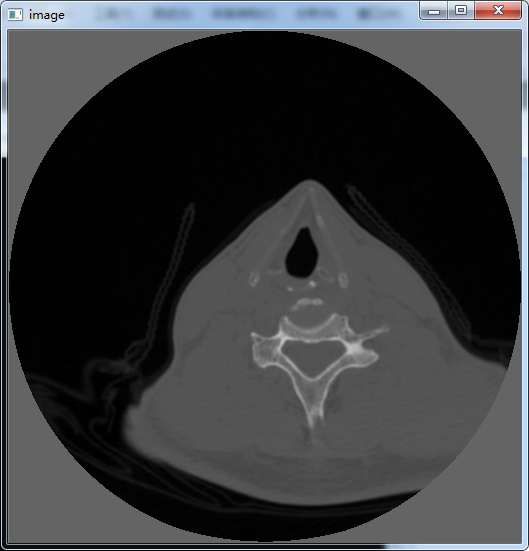

图像的显示

由之前的代码:

1 | DcmElement *element = NULL; |

获取了图像的像素数据,进行进一步的操作:

1 | Uint16* pixData16; |

由数据元素(Data Element)的成员函数getUint16Array()将对应的像素数据存储到无符号整型(unsigned short,即Uint16,又称无符号16位整型)数组中,获得一个向量;再借助OpenCV的创建矩阵和显示图像的功能,进行图像的显示:

1 | for (int i = 0; i < 512*512; i++) |

在创建矩阵之前,进行了灰度拉伸,以提升显示的亮度。

最终效果如上。现在有个问题,在进行数据拉伸的时候,预先已经知道了CT图像的行列值的大小,而应该利用哪个参数或者函数来获取图像的size呢?